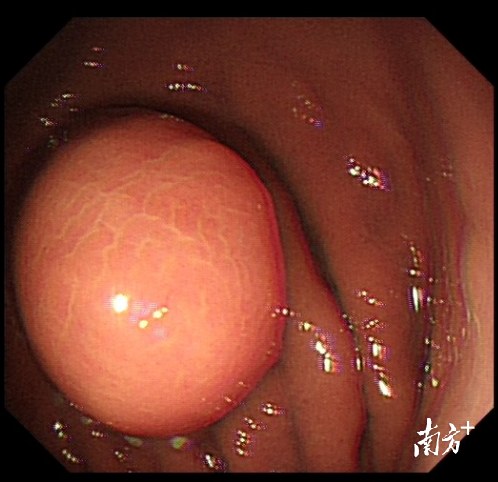

杨女士表示,她今年49岁,家住内蒙古。原是想着自己年纪大了,有必要做个胃肠镜检查,才发现有个直径超过3厘米的胃粘糢下肿物。由于无法判断肿物来源层次及良恶性,不排除需要外科手术切除。

入院后,张卫民主任团队为杨女士制定了详细的诊疗计划,完善术前常规检查。“最重要的是了解肿物在胃的哪个层次,这个问题通过超声内镜可以准确判断。”张卫民介绍,结果提示胃肿物与固有肌层相连,说明肿物位置较深,手术难度较大。

术中,张卫民主任通过胃镜经自然腔道到达肿物,先标记肿物范围,然后逐层剥离肿物,遇到血管会及时电凝或止血钳切断,防止出血。“就像剥洋葱那样把胃里面的肿物剥离出来,过程要克服患者呼吸心跳、胃肠蠕动的干扰,相当于在风浪里剥离肿物。”张卫民主任表示。

在内镜中心和麻醉科的紧密配合下,历时1个多小时成功切除并顺利取出直径超过3厘米大的肿瘤,由于是内镜下微创手术,术后不留手术瘢痕。